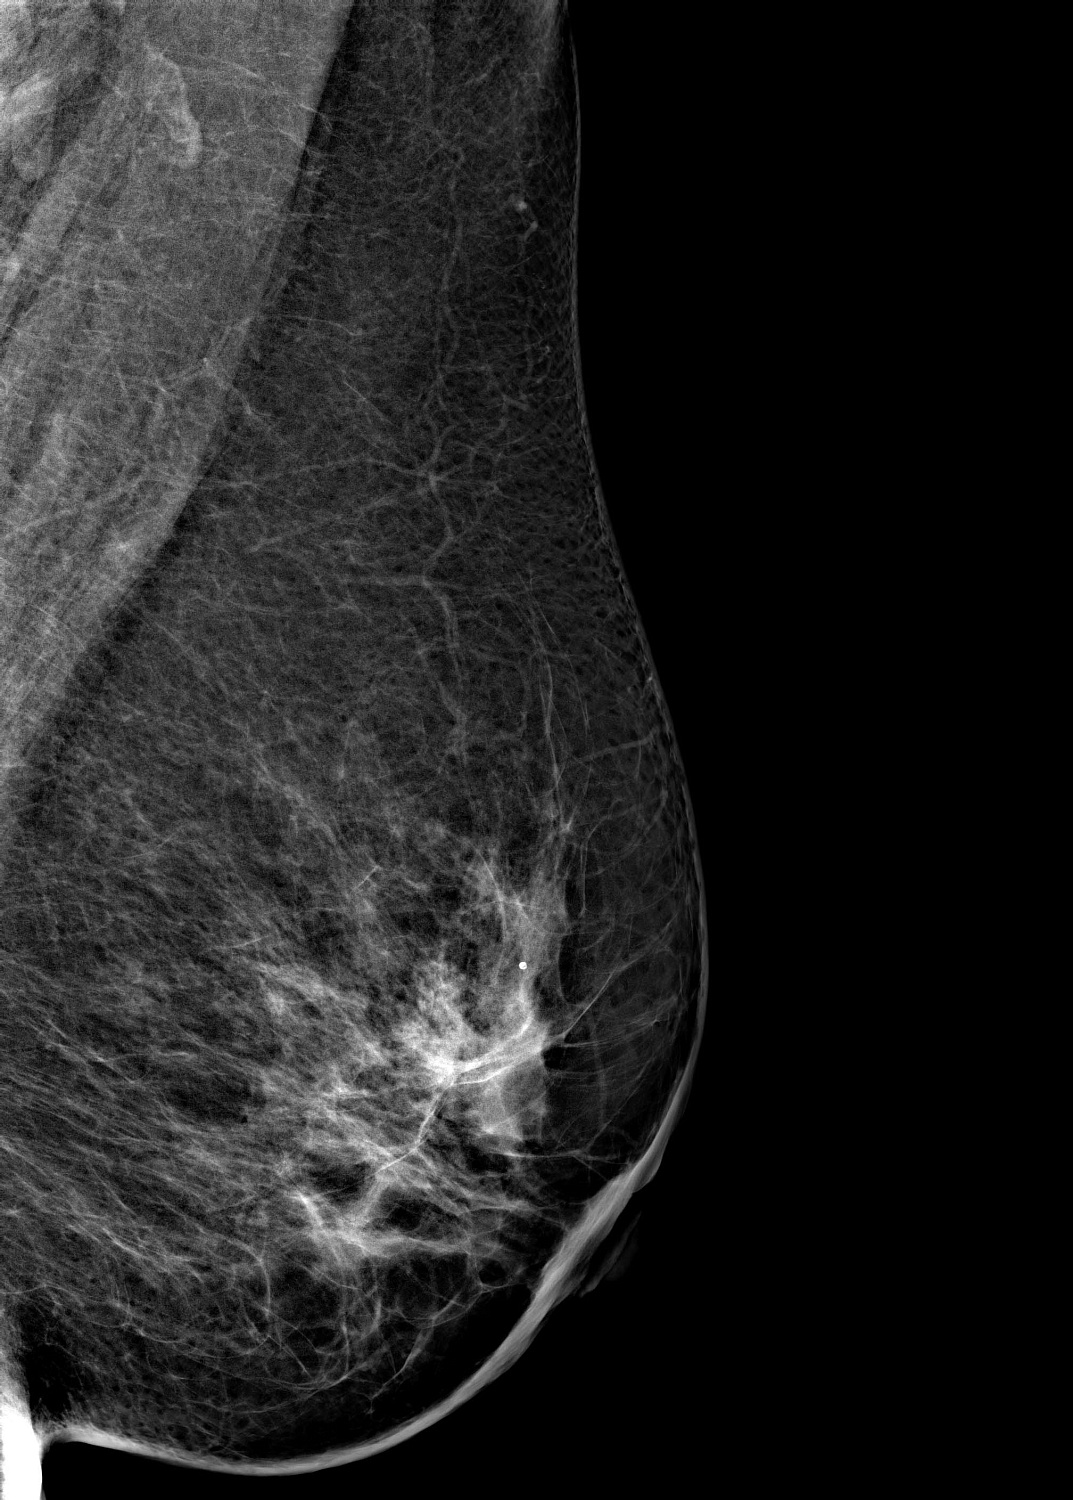

Маммограф выявляет опухоли молочной железы размером от 1-2 мм, которые не определяются при осмотре врача и самообследовании. На снимках хорошо различимы мельчайшие скопления солей кальция (от 87 мкм), тяжистые и другие перестройки тканей, характерные для рака груди 1-2 стадии. Высокую информативность, диагностическую ценность изображений обеспечивает цифровой детектор с самым чувствительным в мире сцинтиллятором. На снимках также определяются воспалительные процессы, кисты и даже небольшие повреждения.

Универсальный размер детектора делает обследование женщин с большим размером груди проще и безопаснее. Функция съемки молочных желез с имплантами позволяет обследовать эту категорию пациенток. На снимках хорошо различимы и ткани груди, и грудные эндопротезы.

Рентгеновский маммограф BRESTIGE EXPERT INDIRECT оснащен чувствительным сенсором непрямого преобразования на основе аморфного кремния. Цифровой детектор этого типа отличается надежностью и обеспечивает высокое качество изображения. Детальная «картинка» получается благодаря активной матрице, содержащей 2816 × 3584 пикселей, и хорошей квантовой эффективности (до 50%). На снимках ясно различимы даже небольшие изменения в структуре тканей и малоконтрастные образования.

Полноформатный детектор облегчает и ускоряет обследование женщин с большими молочными железами, а также делает его безопаснее. Пациенткам с грудью до пятого размера включительно для полноценного исследования достаточно 4 снимков: по 2 для каждой молочной железы. Аппараты, укомплектованные детектором меньшего размера, требуют 8 экспозиций.

Режим позволяет проводить маммографию у пациенток с грудными эндопротезами. На снимках хорошо видны ткани груди. Снимки отражают состояние импланта, в том числе его серьезные повреждения.